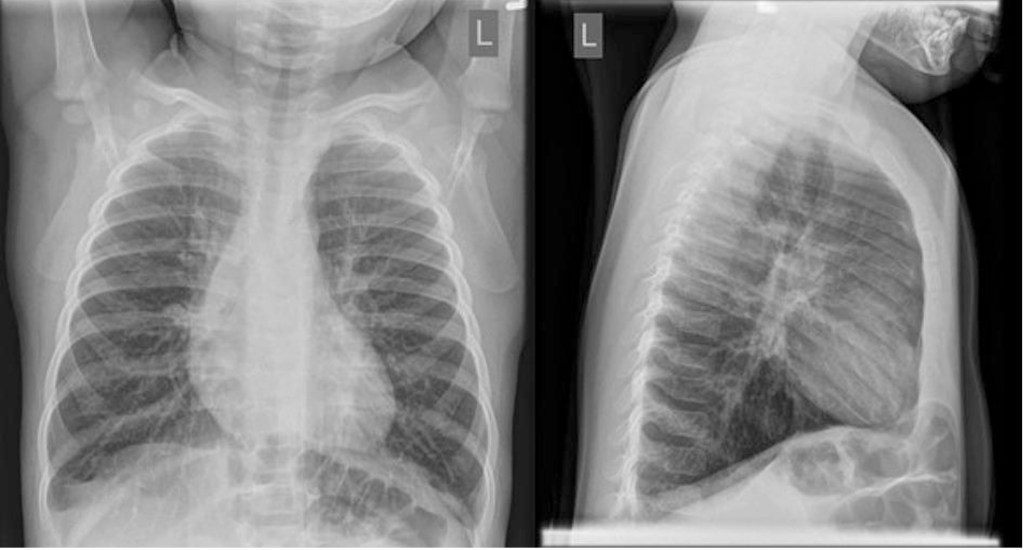

Four days ago, an older sibling who recently started pre-school had a cold. The next day, 6-month-old Zarah fell sick. She has had a runny nose and cough but seemed to be doing fine until yesterday when she did not eat or drink very much. This morning, she had some noisy breathing, and her chest looked funny while she was breathing. When it did not go away after a couple of hours, Zarah’s parents called 811 for advice. They were directed to go to the emergency department. The patient will progress through escalating respiratory support and eventually require intubation and transfer to higher level of care.